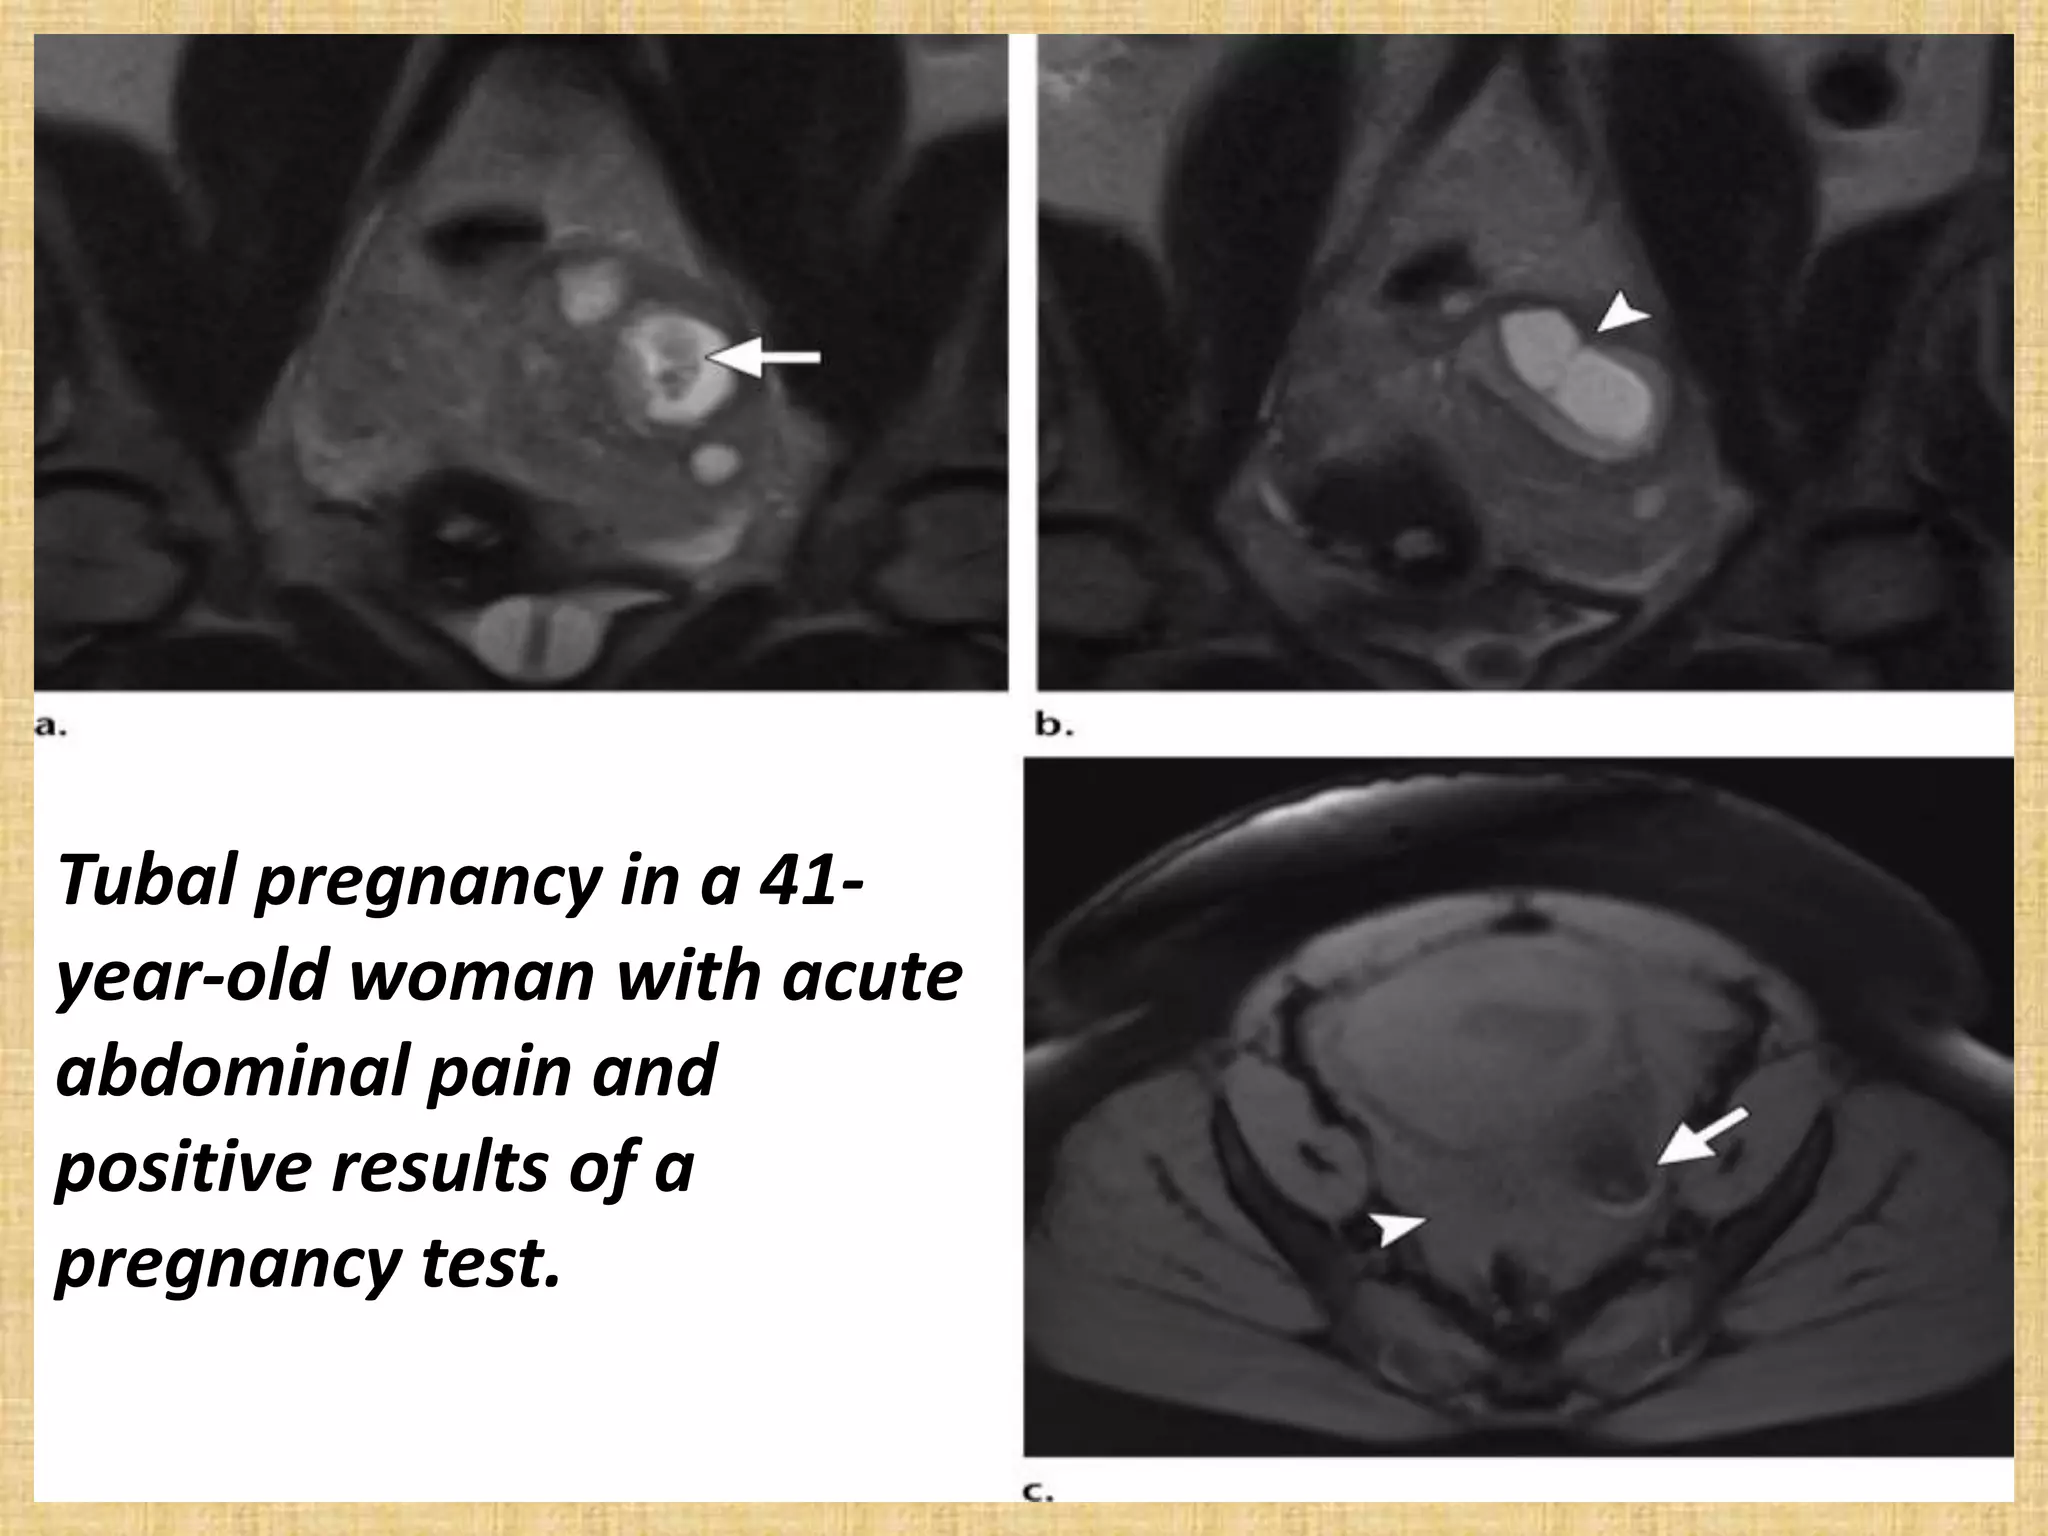

Tubal pregnancy in a 41-

year-old woman with acute

abdominal pain and

positive results of a

pregnancy test.

Tubal pregnancy ina 41- year-old woman with acute abdominal pain and positive results of a pregnancy test.